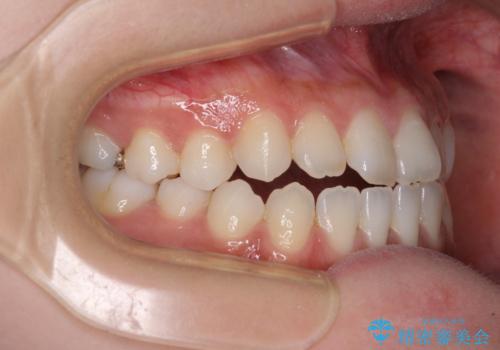

舌突出癖で口元が開いてしまう 舌トレーニングを行ったインビザライン矯正

- 前歯の上下スペースと前歯の隙間を気にして来院された患者様です。

インビザラインにより上下の前歯の隙間を閉じていくこととしました。

上下の隙間に舌が入り込むことが、すきっ歯やオープンバイトの原因であったため、舌の筋肉のトレーニングも並行して行い、後戻りの抑制を図りました。